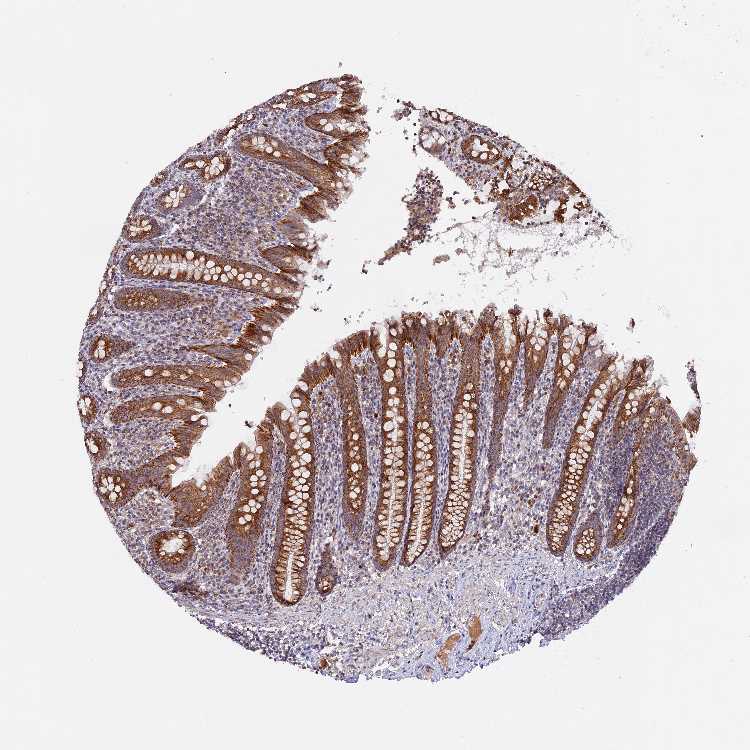

APPENDIX - Antibody stainingi

Antibody staining in the annotated cell types in the current human tissue is reported as not detected, low, medium, or high, based on conventional immunohistochemistry profiling in selected tissues. This score is based on the combination of the staining intensity and fraction of stained cells. Each image is clickable and will lead to virtual microscopy that enables deeper exploration of all samples and also displays staining intensity scores, fraction scores and subcellular localization as well as patient and tissue information for each sample.

Antibody HPA041180

Glandular cells High

Lymphoid tissue Not detected